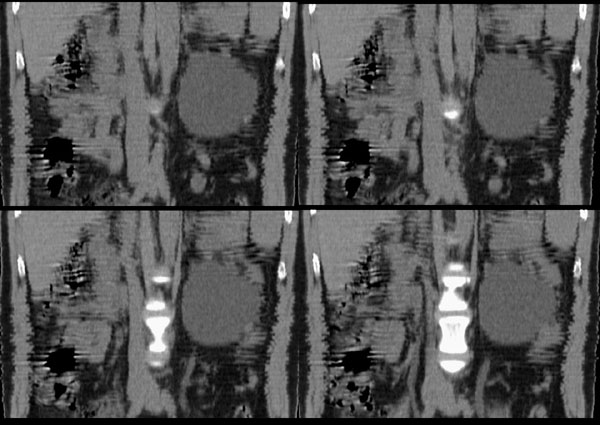

m29y平常体健,无明显不适。单位体检时发现左肾区病变。来我院作ct如下(病人不做增强):

左肾区囊肿冠、矢状重建: